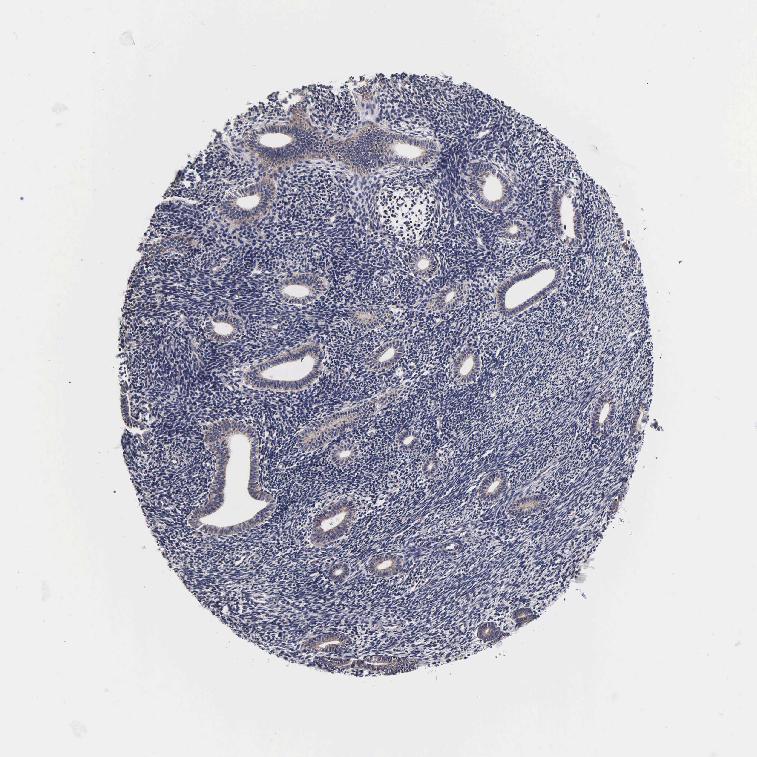

PSMA3